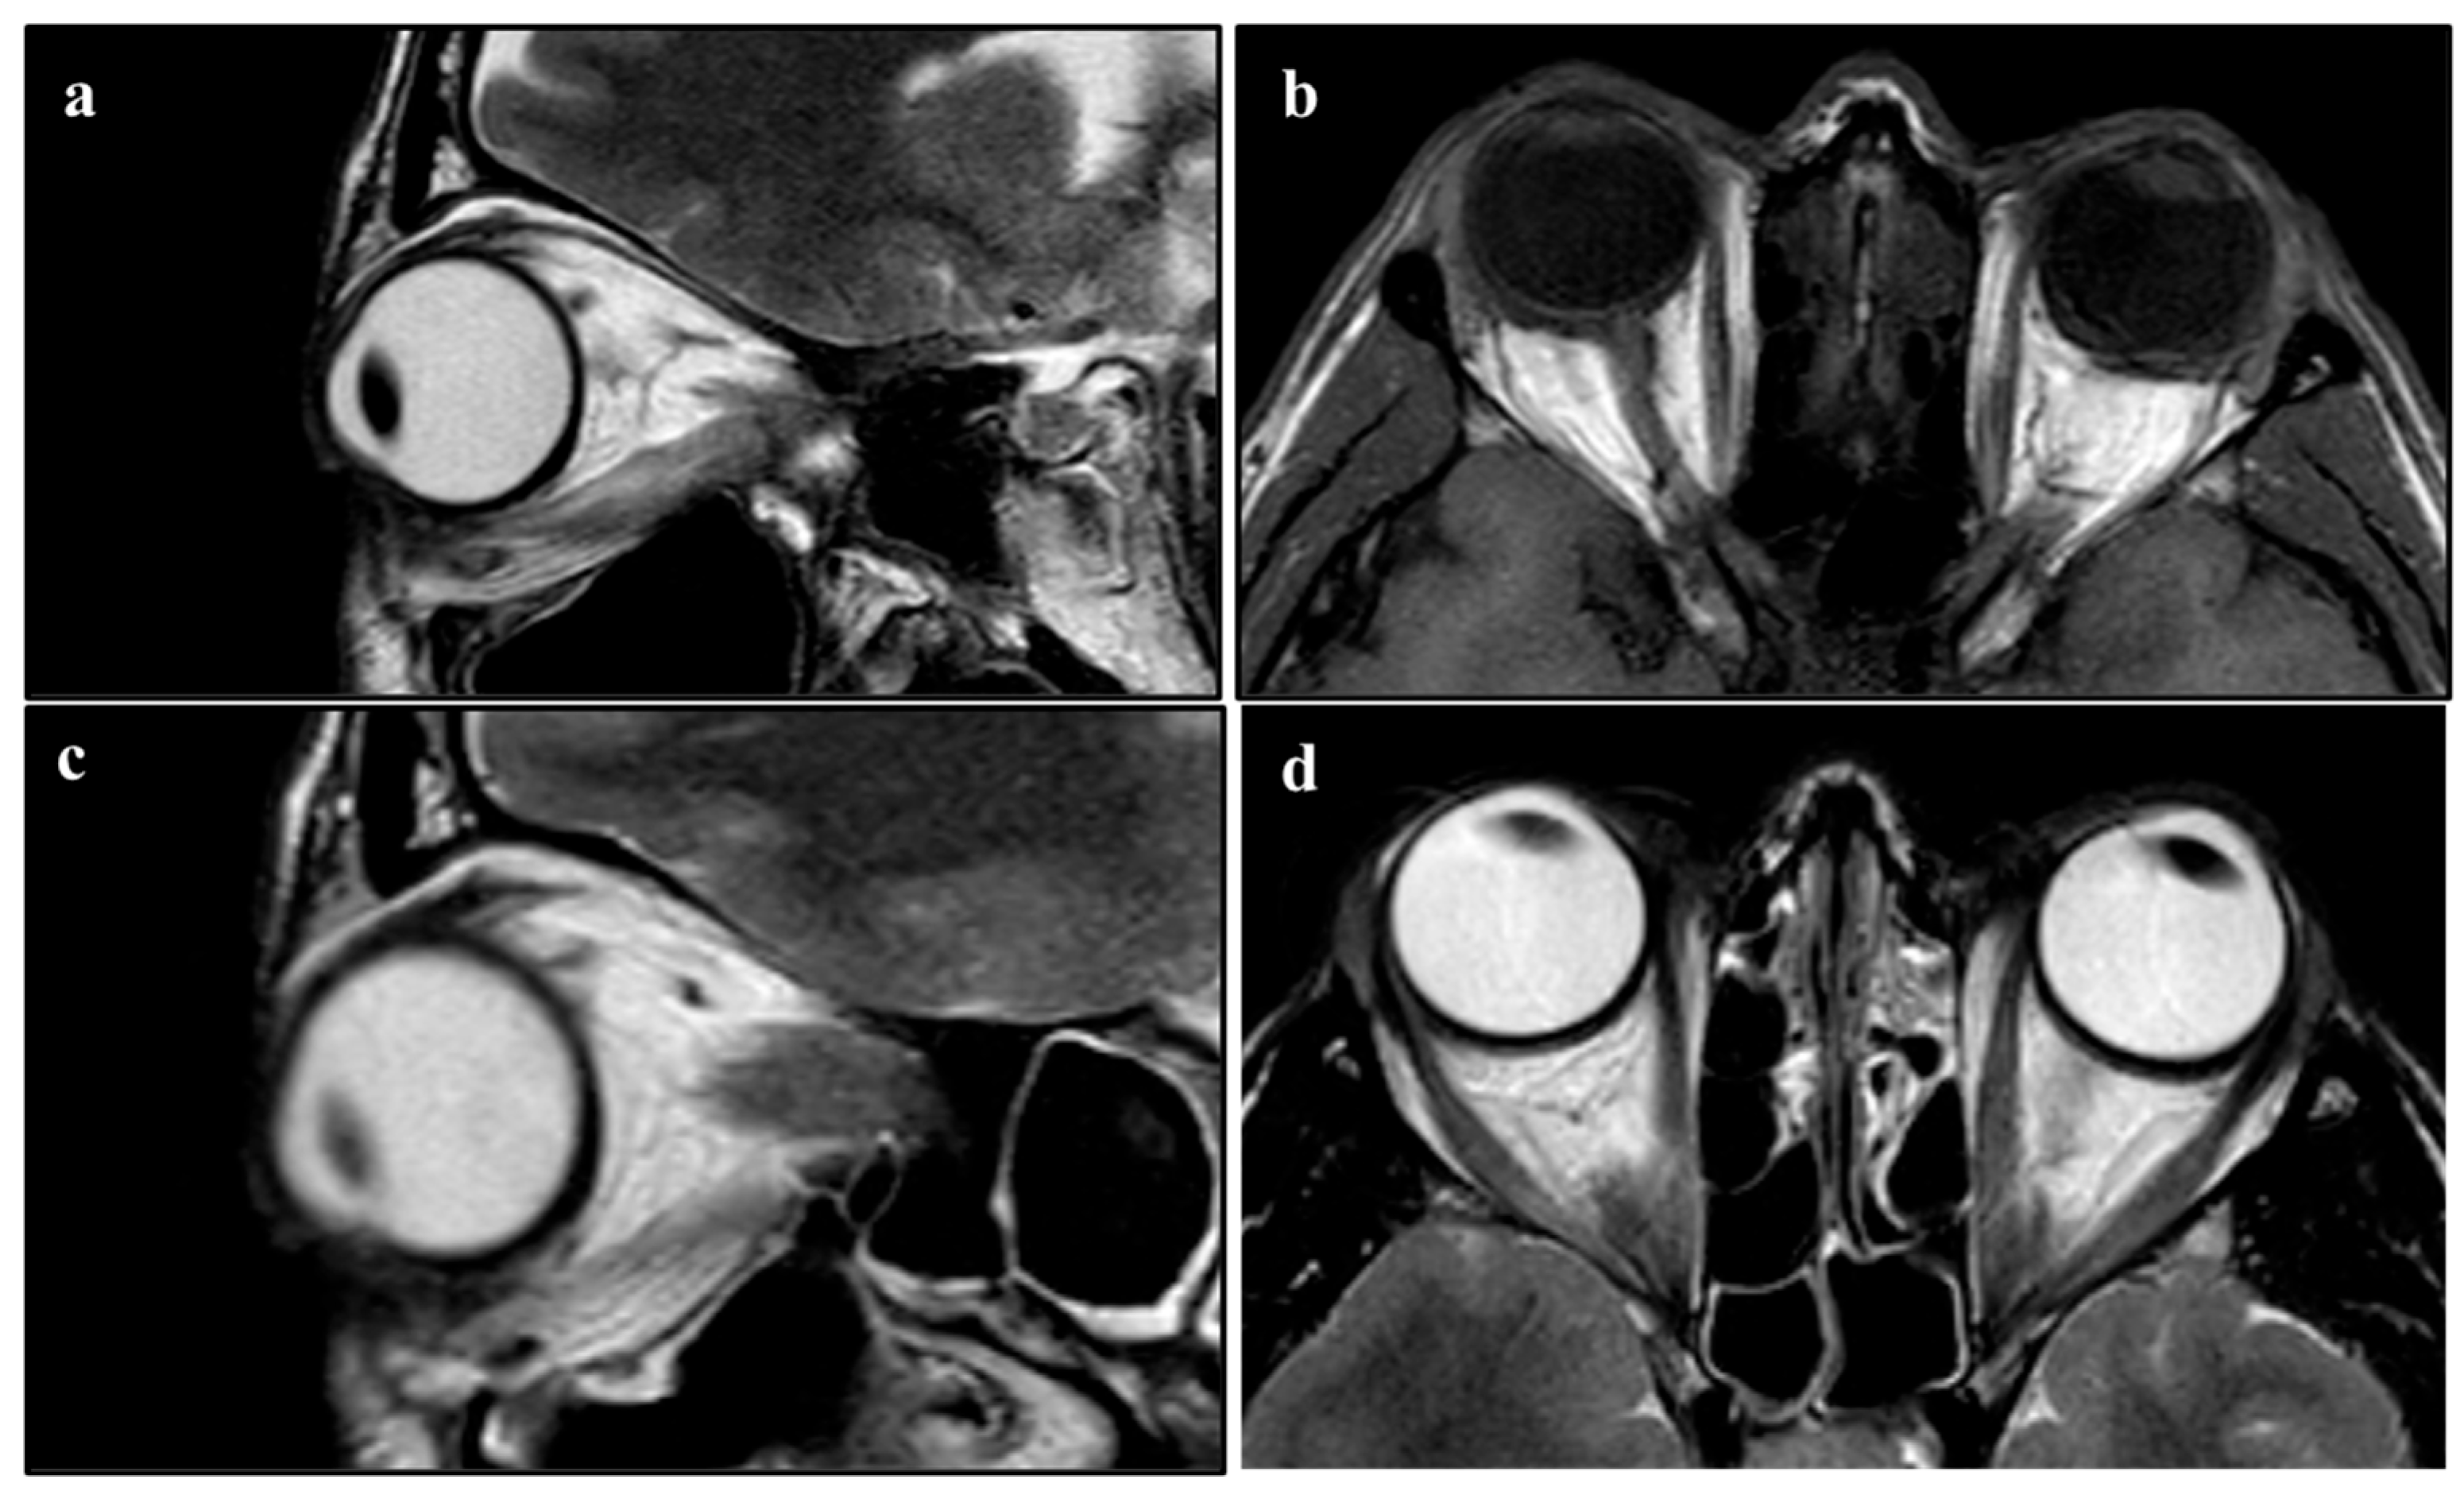

The surgical procedure lasted 1 h, and no complications were reported. After a short period of observation, the patient was discharged. In the first two months after the surgery, no anomalies of interest occurred (Figure 1). After this period, left lagophthalmos was reported and rapidly worsened (Figure 2). Five months after the procedure, a CT scan of the head was performed to find the cause of this adverse event. It showed regular orbital fat and eye muscles and, only in the left eye, thickened eyelids (Figure 3). In the following months, MRI scans were performed, finding a bilateral increase in the thickness of the eye muscles (Figure 4).

Figure 4.

(a,b) NMR performed 10 months after surgery. (a) Sagittal view. (b) Coronal view. (c,d) NMR performed 12 months after surgery. (c) Sagittal view. (d) Coronal view.